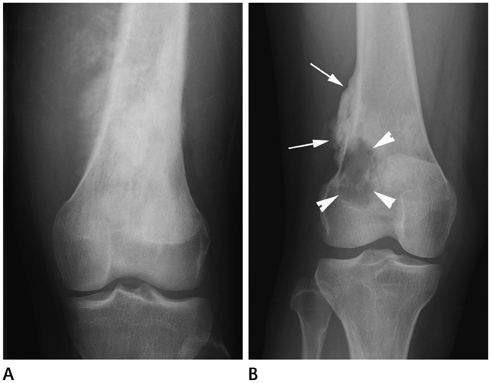

Systematic Approach of Sclerotic Bone Lesions Basis on Imaging Findings

- Sclerotic bone lesions are common, but there are diverse groups of tumors and non-tumorous lesions. Although plain radiograph and computed tomography can reveal important characteristics of these lesions, diagnosis is often challenging for radiologists. A systematic approach and familiarity with the imaging features of various sclerotic bone lesions may be greatly helpful for eliminating in the differential diagnosis. This review describes the systematic approach to diagnosing sclerotic bone lesions based on imaging findings.